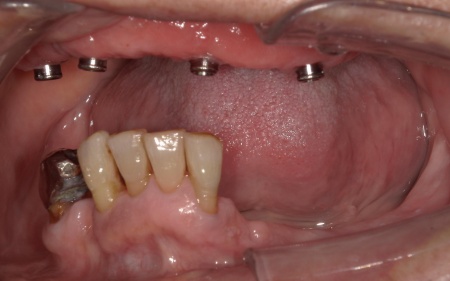

まず、上顎の状態や残存歯について詳しく検査し、温存が難しいと判断した左上の歯3本(犬歯、第1小臼歯、第2小臼歯)を抜きました。

抜歯後は、即時インプラント埋入手術を実施しています。

インプラント埋入後は経過観察を行い、歯茎と顎の骨が治癒するのを待ちます。

傷が治り、インプラントが顎の骨にしっかりと結合したことを確認したら、インプラントの頭部分に入れ歯と連結するための部分となる「アタッチメント」を装着しました。